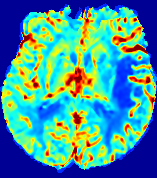

LesionRefer to captionRefer to captionRefer to captionRefer to captionRefer to captionRefer to caption𝐕rgbsubscript𝐕𝑟𝑔𝑏{\bf{V}}_{rgb}Refer to captionRefer to captionRefer to captionRefer to captionRefer to captionRefer to caption𝐕2subscriptnorm𝐕2{\|\bf{V}}\|_{2}Refer to captionRefer to captionRefer to captionRefer to captionRefer to captionRefer to captionRefer to caption3.53.53.52.82.82.82.12.12.11.41.41.40.70.70.70.00.00.0(mm/s)𝑚𝑚𝑠(mm/s)D𝐷DRefer to captionRefer to captionRefer to captionRefer to captionRefer to captionRefer to captionRefer to caption0.0200.0200.0200.0160.0160.0160.0120.0120.0120.0080.0080.0080.0040.0040.0040.0000.0000.000(mm2/s)𝑚superscript𝑚2𝑠(mm^{2}/s)Slice #1Slice #2Slice #3Slice #4Slice #5Slice #6

Figure 3: PIANO feature maps for one stroke patient, where the lesion is located in the left hemisphere. Top row: segmented stroke lesion region (white) on different slices, obtained from ISLES 2017. The corresponding slices for the PIANO feature maps are shown in the following rows.

For a better insight into an estimated velocity field 𝐕𝐕{\bf{V}} and diffusion field 𝐃𝐃{\bf{D}}, we compute the following maps: (1) 𝐕rgbsubscript𝐕𝑟𝑔𝑏{\bf{V}}_{rgb}: Color-coded orientation map of 𝐕=(Vx,Vy,Vz)T𝐕superscriptsuperscript𝑉𝑥superscript𝑉𝑦superscript𝑉𝑧𝑇{\bf{V}}=(V^{x},V^{y},V^{z})^{T}, obtained by normalizing 𝐕𝐕{\bf{V}} to unit length and mapping its 3 components to red, green, blue respectively; (2) 𝐕2subscriptnorm𝐕2\|{\bf{V}}\|_{2}: 222 norm of 𝐕𝐕{\bf{V}}; (3) D𝐷D: scalar field in Eq. 5.

Fig. 3 and Fig. 4 show the PIANO feature maps estimated from two ISLES 2017 patients: all are highly consistent with the lesion in both cases. Details of the blood flow trajectories are revealed in 𝐕rgbsubscript𝐕𝑟𝑔𝑏{\bf{V}}_{rgb} by the ridged patterns and the sharp changes of colors in the unaffected (right) hemisphere, while the flat patterns appearing within the lesion provide little directional information about the velocity and indicate low velocity magnitudes. Velocity magnitudes are more directly visualized via 𝐕2subscriptnorm𝐕2\|{\bf{V}}\|_{2}, from which one can easily locate the lesion where 𝐕2subscriptnorm𝐕2\|{\bf{V}}\|_{2} is low. D𝐷D also indicates lower diffusion values in the lesion, though with less contrast potentially due to the fact that it captures the accumulated effect of CA diffusion at the voxel-level.